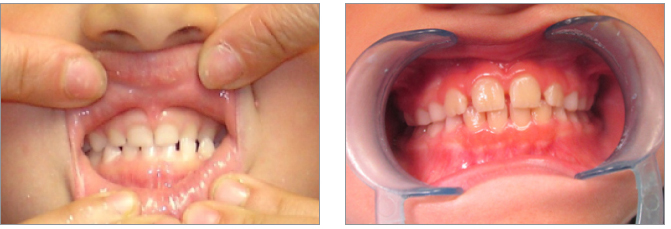

7) La terapia precoce deve eliminare elementi patogenetici di aggravamento come l’interposizione linguale

8) La precoce correzione del morso inverso elimina laterodeviazioni funzionali mandibolari

9) L’esecuzione di impianti è indicata nei casi di agenesia dei laterali. E’ necessario tenere conto anche dell’estetica complessiva del volto